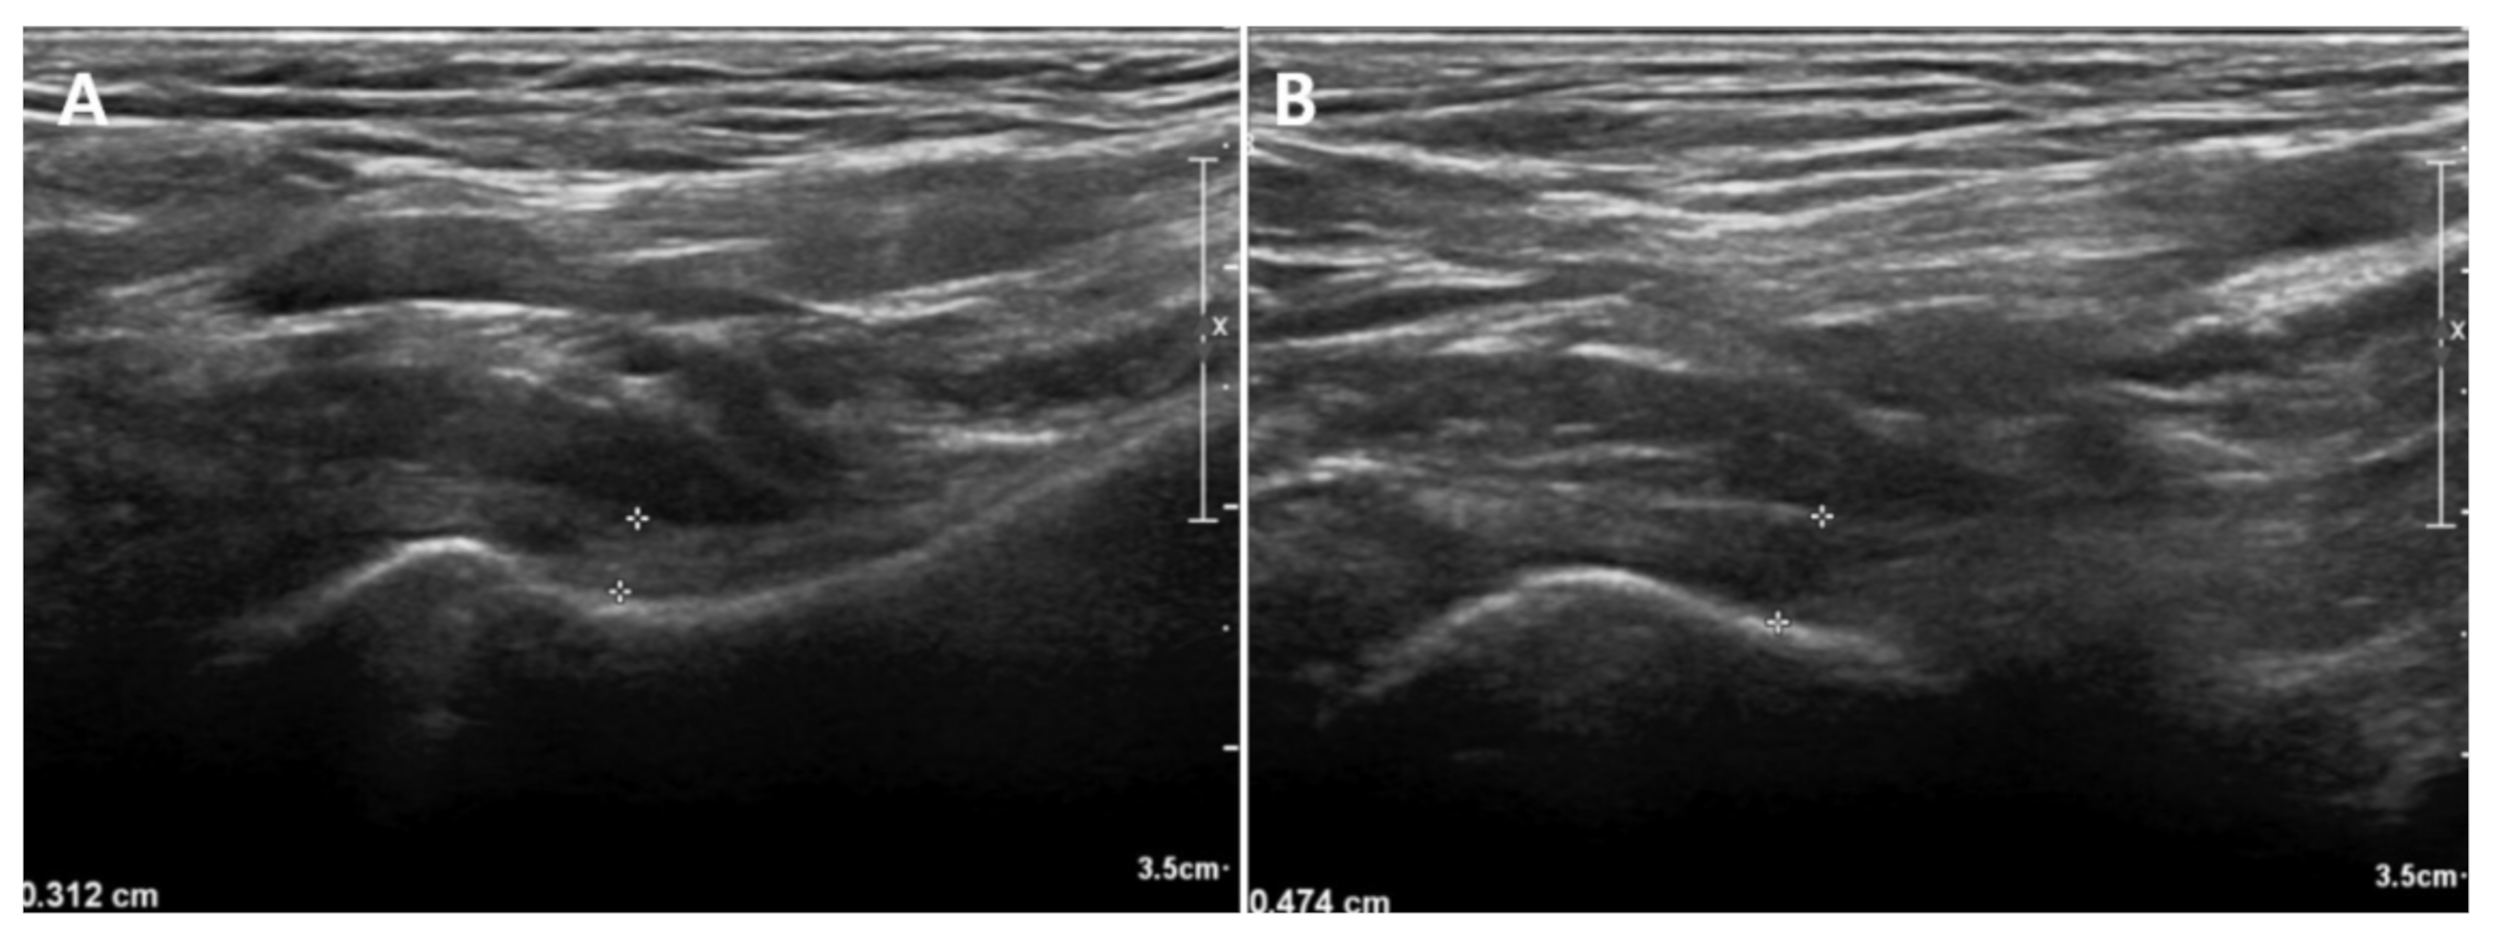

2.2. Us Protocol and Arm Positions

3.2. Comparison of the IJC Thickness on Us between the Affected and Unaffected Shoulders

3.3. Comparison of the IJC Thickness on Us Depending on Arm Position